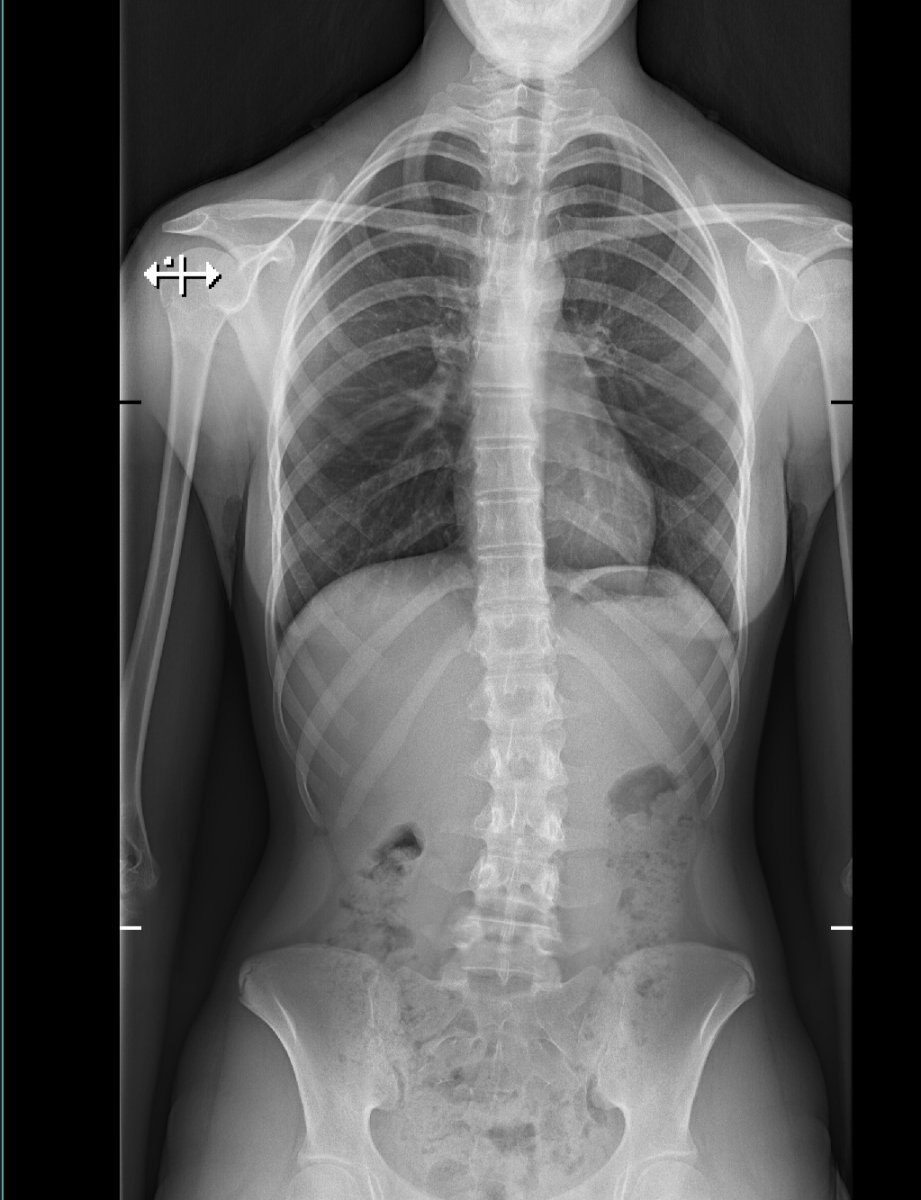

Dacht ik ook ja. Ifbb pro Mascha Tieken heeft dat ook.Je kunt met training veel verbeteren en evt een brace. oud forumlid @Tatsu had het geloof ik ook, maar een goede orthopeed kan je gericht advies geven. Neem ook aan dat je via een orthopeed foto's hebt laten maken

Dat zal de orthopeed je aangeven. en herstel heb ik al aangegeven, zeker omdat ze nog niet volgroeid is.Weet iemand of dit een erge vorm van scoliose is? Men drukt dit uit in graden. Dit lijkt me maar een paar graden. Zou het kunnen dat met sport en en brace dit bijna volledig weggaat? Ze is bijna 15 en 1m60 ongeveer

Nee volgens mij niet extreem maar lijkt wel forward head posture schouders naar voren enzo. Zou daar ook op letten. Of moest ze deze houding aanhouden voor de foto?Weet iemand of dit een erge vorm van scoliose is? Men drukt dit uit in graden. Dit lijkt me maar een paar graden. Zou het kunnen dat met sport en en brace dit bijna volledig weggaat? Ze is bijna 15 en 1m60 ongeveer

Weet iemand of dit een erge vorm van scoliose is? Men drukt dit uit in graden. Dit lijkt me maar een paar graden. Zou het kunnen dat met sport en en brace dit bijna volledig weggaat? Ze is bijna 15 en 1m60 ongeveer

Zou het kunnen dat ze dit heeft ontwikkeld door het kunstschaatsen. Altijd op dat ene been, en het andere been steil naar achteren en naar boven...vele jumps....thuis trainde ze uren lang in de woonkamer...altijd dus die schuine stand.... Ze is altijd zeer sportief geweest.Als ik zo vergelijk met andere röntgenfotos dan is dit heel mild, maar goed, dat kan de arts wel vertellen. Lijkt mij dat er nog veel mogelijk is vanwege haar leeftijd. Sterkte in ieder geval!

Zou het kunnen dat ze dit heeft ontwikkeld door het kunstschaatsen. Altijd op dat ene been, en het andere been steil naar achteren en naar boven...vele jumps....thuis trainde ze uren lang in de woonkamer...altijd dus die schuine stand.... Ze is altijd zeer sportief geweest.